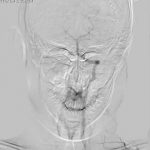

وأوضحت الدكتورة الجاسم أنه بدأ تحضير المريض للعمل الجراحي بإجراء تصوير الأوعية بالطرح الرقمي بإشراف اختصاصي الجراحة العصبية وتحضير وحدات الدم اللازمة ثم إزالة الورم بالكامل بطريقة الجراحة التنظيرية بنظام ملاحة ثلاثي الأبعاد بالتنظير الداخلي لافتة إلى أن الحالة العامة للمريض جيدة ويتماثل للشفاء.

وأوضحت الدكتورة الجاسم أنه بدأ تحضير المريض للعمل الجراحي بإجراء تصوير الأوعية بالطرح الرقمي بإشراف اختصاصي الجراحة العصبية وتحضير وحدات الدم اللازمة ثم إزالة الورم بالكامل بطريقة الجراحة التنظيرية بنظام ملاحة ثلاثي الأبعاد بالتنظير الداخلي لافتة إلى أن الحالة العامة للمريض جيدة ويتماثل للشفاء.